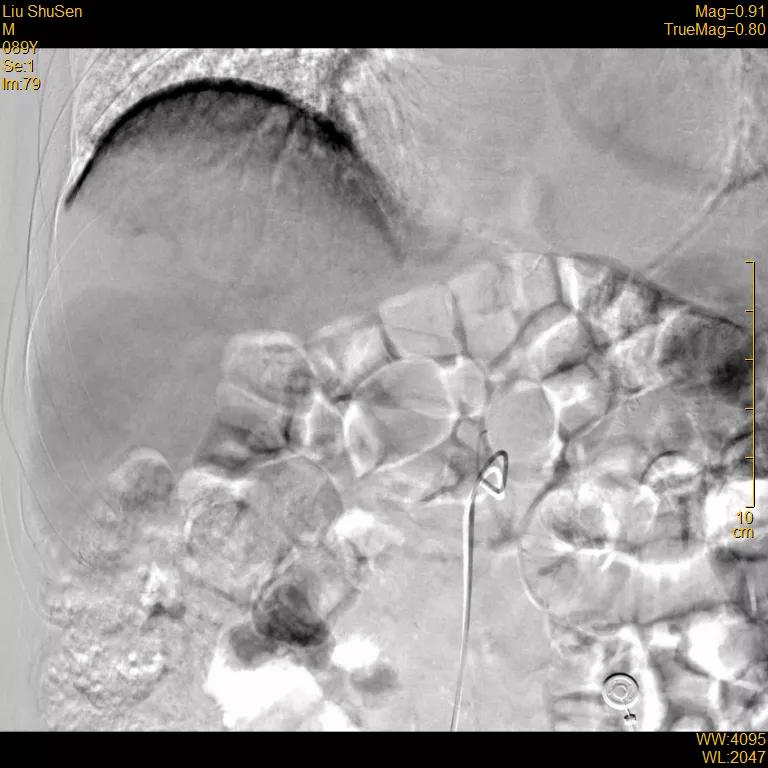

超选至肝右动脉分支1造影+栓塞

栓塞材料:表柔比星60mg+载药

微球;明胶海绵

文章图片